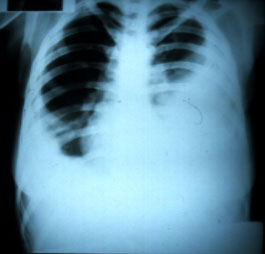

| Paroniquía en quinto dedo mano derecha | En la radiografía de tórax postero-anterior se observó paquipleuritis bilateral. |